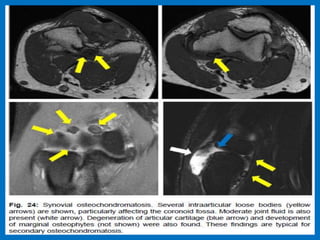

Large osteochondral lesion in the lateral trochlea (yellow arrows).

Notice the edema in the subchondral bone (red arrow).